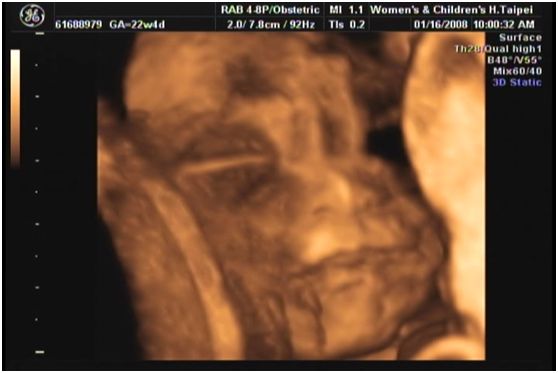

今天早上去醫院照了高層次超音波, 好像就是所謂的3D立體超音波,